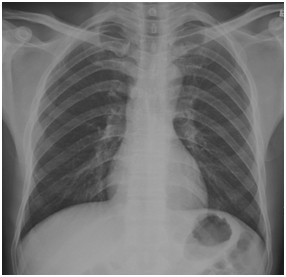

01卷-5.根據(jù)下圖請做出正確診斷(本題滿分2.00分)

A.正常胸片

B.肺門淋巴結(jié)腫大

C.肺炎

D.主動脈型心(靴型心)

本題答案:A

【該題針對“ X線-正常胸片 ”知識點進行考核】